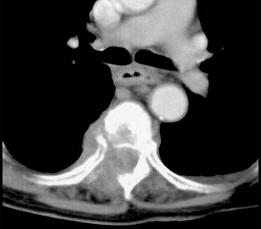

问题 女,72岁,双下肢轻度截瘫3个月余,请结合影像学检查,选出最可能的诊断 ( )

选项 A、脊柱转移瘤 B、强直性脊柱炎 C、脊椎结核 D、化脓性脊柱炎 E、椎体压缩骨折

答案 C